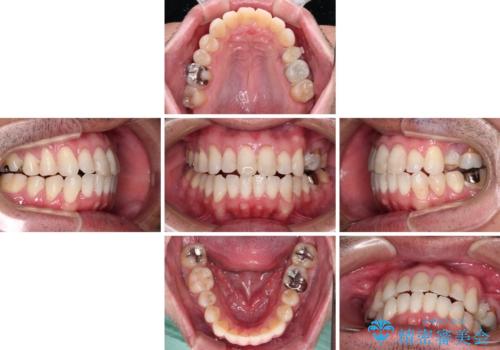

内側に転位した歯とボロボロのむし歯 インビザラインによる矯正治療とむし歯治療

- ボロボロのむし歯とデコボコの歯列を気にして来院された患者様です。

ボロボロとなっていた歯は抜歯が必要な状態でしたが、舌側転位している歯を移動させることで抜歯スペースを埋めることができるため、矯正治療により歯列を整えることとしました。

舌側転位の改善にインビザラインを用いるのはやや難易度が高くなりますが、前歯部のデコボコは軽度であったため、インビザラインによる矯正治療を行うこととしました。

矯正治療後には抜歯が必要な歯に隣接してむし歯となっていた歯をオールセラミッククラウンにて補綴治療を行うこととしました。

矯正治療開始時に、インビザライン矯正の加速装置を購入されましたが、インビザライン自体をあまりしっかりと使用できず、4年間の治療期間となりました。